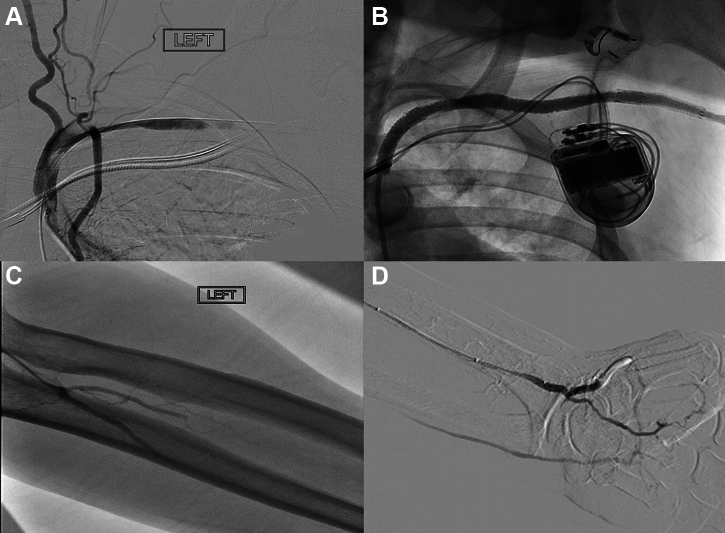

Figure 7.

Dissection. A) Angiography showing extensive dissection and thrombosis of the left subclavian artery. B) After extensive thrombectomy, angioplasty and stenting of the left subclavian and axillary artery. Note thrombus shift into the vertebral and left internal mammary artery which was asymptomatic C) Distal embolization to the left radial, ulnar and interosseous arteries D) Restoration of flow to all 3 forearm arteries after aspiration thrombectomy and low-pressure balloon angioplasty.